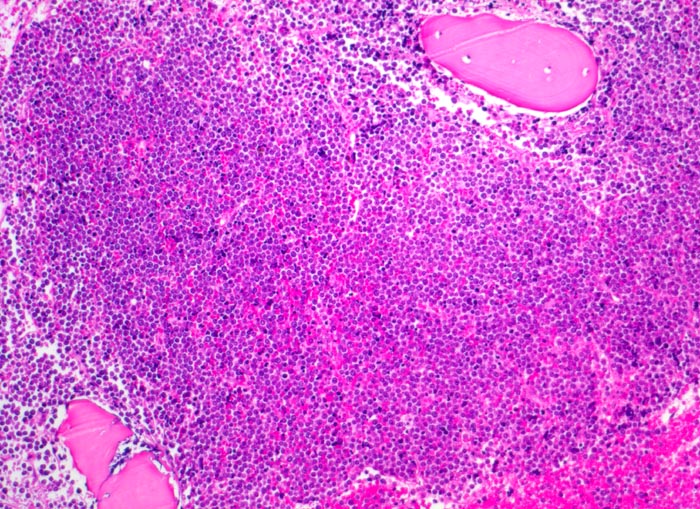

Morphologische Merkmale:

• Partielle Verdrängung des Fettmarks durch monomorphen Blastenrasen (Zellularität ca. 80%).

• Verdrängung der Myelo-, Erythro- und Megakaryopoese.

• Mittelgrosse Lymphoblasten mit wenig Zytoplasma.

• Kerne mässig polymorph, oval, teils mit Kerneinkerbungen. Feine Nukleolen. Lockeres Chromatin.

• Zahlreiche Mitosen.